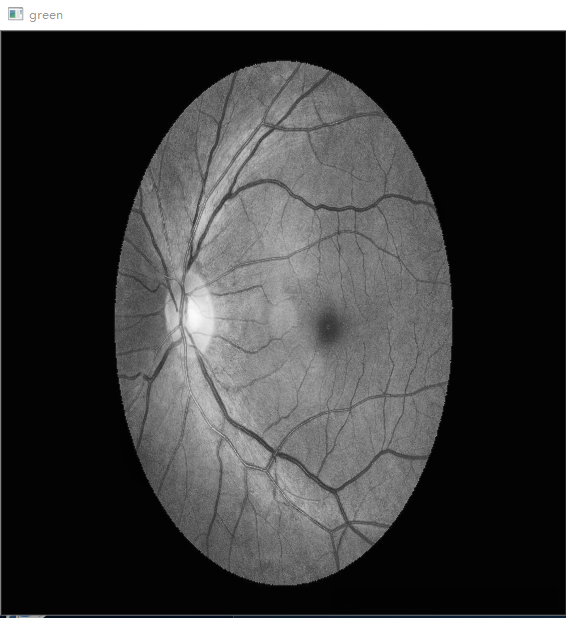

# 进行 CLAHE 处理,提取绿色通道

clahe = cv2.createCLAHE(clipLimit=2.0, tileGridSize=(8, 8))

img_clahe_green = clahe.apply(g)

cv2.imshow('green', img_clahe_green)